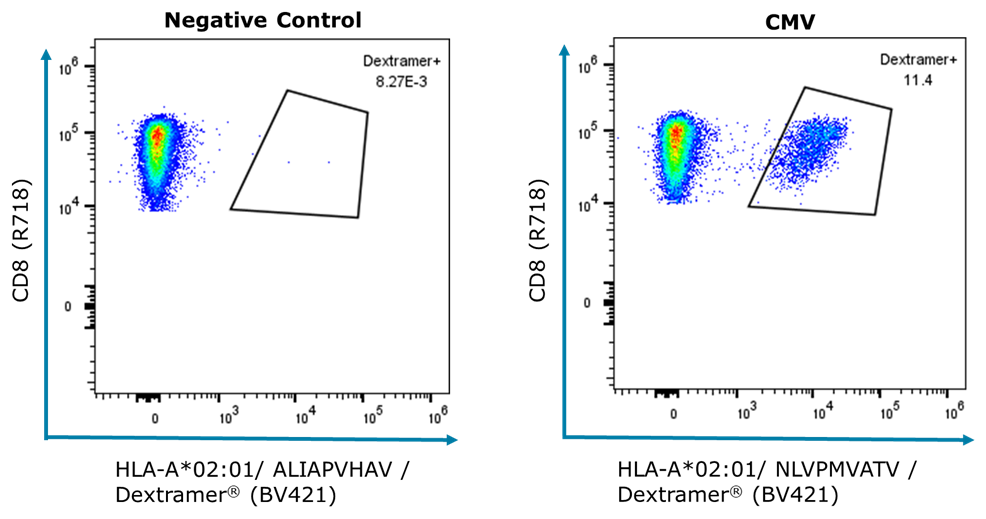

High T Cell Response in Latent CMV Infection

We observed a high T-cell response to CMV in the PBMC sample. CMV-specific T cells make up 11% of all CD8+ T cells, which is common in healthy individuals with latent infection.

It is a feature of CMV infections that T-cell responses do not contract after primary infection and that the number of CMV-specific cells remains high and even increases with age. This is a phenomenon known as “memory T cell inflation”.